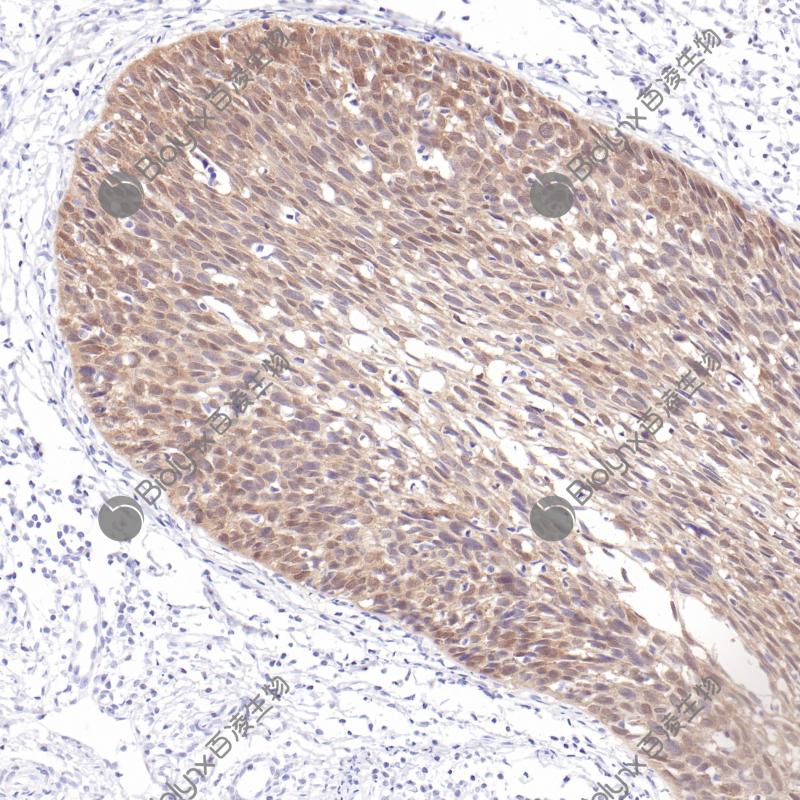

间皮瘤BAP-1(BP6255)染色

BAP-1 (BRCA-1相关蛋白-1)是一种80 kDa的蛋白质,它通过靶向降解或改变其他蛋白质的活性功能来去除泛素修饰物。因此,BAP-1有助于参与调节不同细胞过程的靶蛋白功能。BAP1基因的种系突变已被确定为一种新型的肿瘤易感综合症的遗传驱动力,其导致遗传性、早发性癌症的风险增加。BAP-1与多种类型癌症的早发和/或风险增加有关,包括膜黑色素瘤、恶性间皮瘤、结肠癌和肾细胞癌。

细胞核